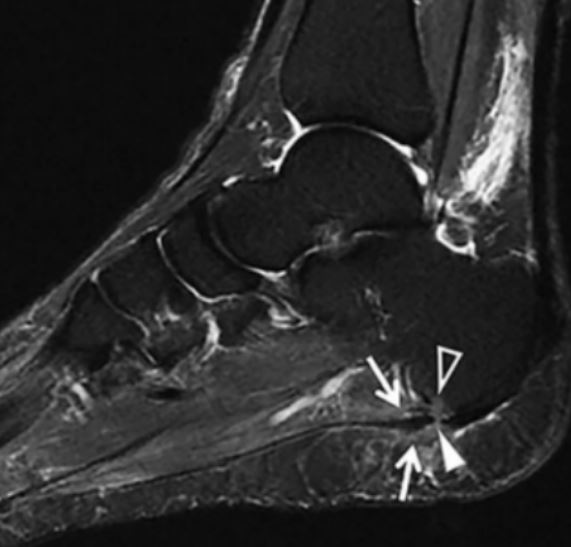

2. MRI检查可见跖腱膜增厚、水肿。MRI可清楚地显示软组织与骨性结构,可以有助于不典型足跟痛或顽固性足跟痛的诊断。